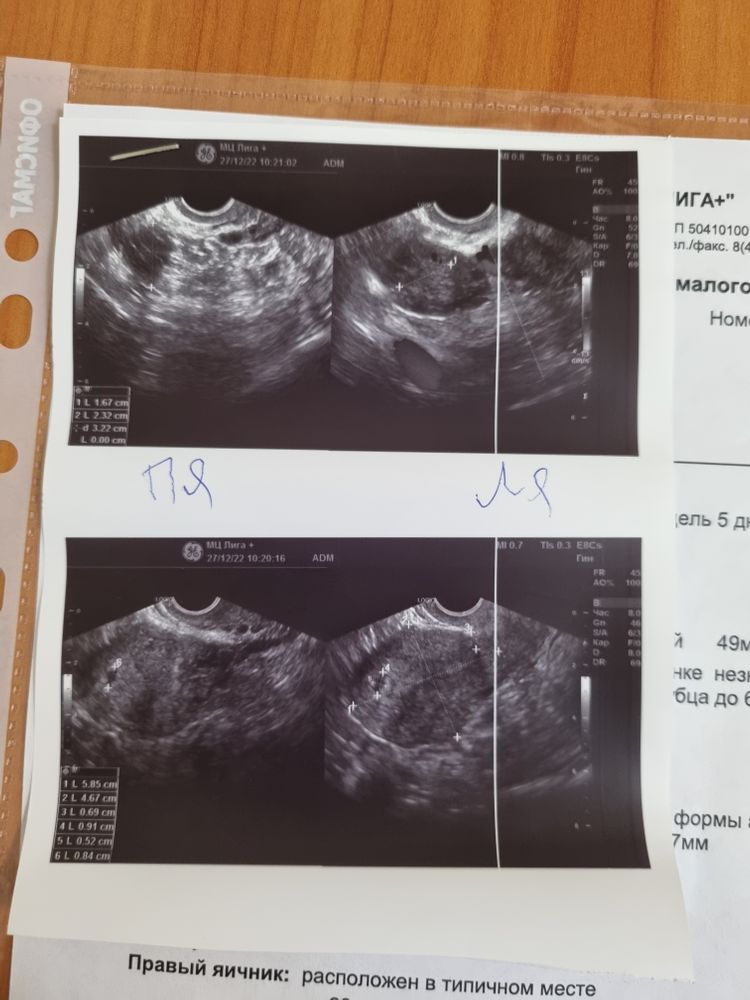

У Вас на фото сердечко))) На верхнем справа. Мои поздравления 🎉🎉🎉

Кажется получилось #2 Пять недель второй (третьей) беременности 🤞